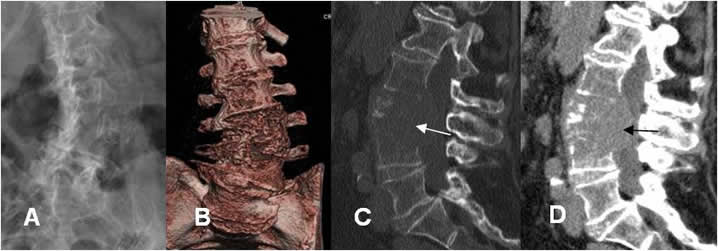

Fig 22. TAC 3D.

A: Rx AP y B: TAC reconstrucción 3D. Rotoescoliosis lumbar izquierda, con alteración en la densidad y configuración de los cuerpos inferiores.

C: TAC reconstrucción sagital en ventana de hueso y D: en ventana de tejido. Existe lesión lítica lumbar, que compromete varios cuerpos vertebrales y masa de tejidos blandos que invade el canal medular, por metástasis de tumor de mama.